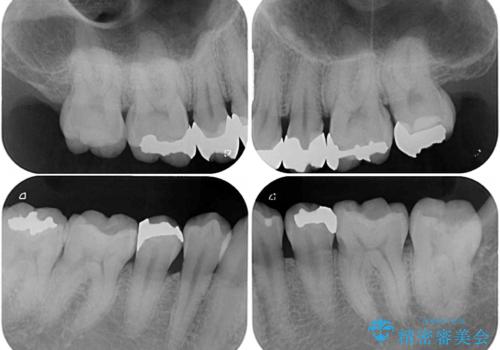

- 奥歯の目立つ銀歯と上下前歯の叢生と隙間を気にして来院された患者様です。

開咬の治療は、前歯を閉じるように動かすとともに、上下臼歯を圧下(骨内にめり込ませる)させることで進めて行きます。

インビザラインは臼歯の圧下を効果的に行えるため、インビザラインを用いて矯正治療を行うこととしました。

銀歯については、矯正治療により咬合関係を改善し、矯正治療後半に修復治療を行うこととしました。